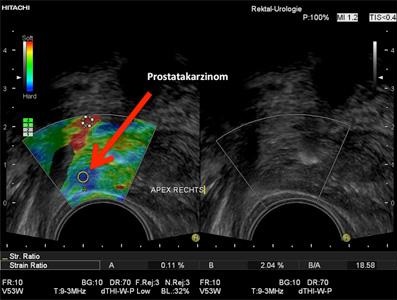

ELASTOGRAPHIE

Ein Verfahren zur verbesserten Erkennung des Prostatakarzinoms ist die Elastographie. Bei diesem Ultraschallverfahren wird die Prostata durch eine transrektale Ulltraschallsonde mit sanften Druckbewegungen komprimiert und dekomprimiert.

Tumorgewebe ist im Vergleich zu normalem Prostatagewebe härter und lässt sich daher weniger leicht komprimieren. Dieses Phänomen wird vom Ultraschallgerät verarbeitet und farbkodiert dargestellt.

Harte, und somit krebsverdächtige Areale, erscheinen blau. Bei der routinemäßig durchgeführten 10-12- fach Biopsie der Prostata wird nach einem festen Schema „blind“ in die Prostata gestochen. Hierdurch kann in vielen Fällen ein vorhandenes Karzinom übersehen werden.

Durch die Elastographie wird im Rahmen der Prostatabiopsie bei Tumorverdacht eine höhere Erkennungsrate von Tumoren erreicht.